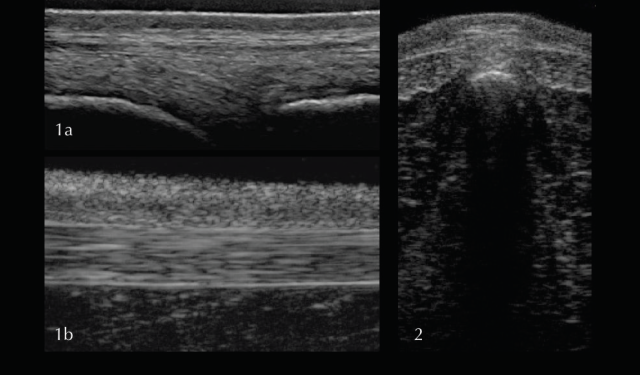

For the supra- and interspinous ligaments (SSL and ISL) longitudinal views are most useful. The images are best acquired with a high-frequency linear transducer using a stand-off pad. The head should be kept in a neutral position as high head carriage may cause relaxation of the SSL and therefore a hypoechogenic appearance. Superficial fibres of the SSL have a horizontal orientation whereas deep fibres of the ISL run in caudoventral direction appearing hypoechogenic in comparison. Care should be taken to position the probe exactly midline at the level of the dorsal spinous processes. The aponeuroses of the epaxial musculature can be imaged off-midline with a parallel fibre pattern similar to the SSL.

In the thoracic (saddle) region the SSL is thin and wide, whereas further caudal in the lumbar region the ligament is thick and narrow with a more echogenic, homogenous appearance. The transverse view of the SSL is less useful due to being more prone to artifacts. In order to achieve the best image quality, the transducer should be tilted cranially and caudally. Published scientific data about the ultrasonographic appearance of the SSL in normal horses and horses with back pain offering information about the potential clinical significance is limited (Henson et al 2007). The clinical significance of heterogenous regions in the SSL should therefore be questioned and further tests, such as diagnostic local anaesthesia, should be applied.